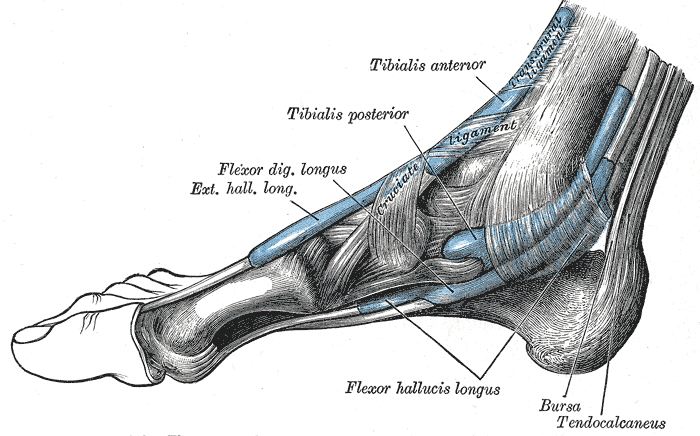

Common Foot & Ankle Disorders

Did you know the foot has 26 bones, 33 joints, 107 ligaments, 19 muscles, and numerous tendons? These parts all work together to allow the foot to move in a variety of ways while balancing your weight and propelling you forward or backward on even or uneven surfaces. It is no wonder that 75 percent of all Americans will experience foot problems at one point or another in their lifetimes.